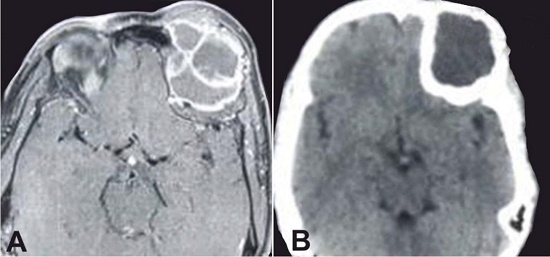

A 35-year-old female presented with left fronto-orbital swelling of 10 years’ duration. She had progressive deterioration of vision in the left eye for 1.5 years, and could barely perceive hand movements close to face. The proptosis increased over the last month. The left eye was displaced inferiorly and medially. No endocrine abnormalities were detected. Radiology revealed a lesion involving the orbital roof, the frontal bone, and the sphenoid wing (Figures 1A and 1B).

The patient was operated on through a twin-piece craniotomy. Intraoperatively, the lesion was found to be of variable consistency with fibrous, fleshy, and cystic areas. The morphological features at the time of the intraoperative frozen section suggested a meningioma (Figures 2A and 2B).

Computed tomography showed a bony expansion and the presence of multiloculated cystic swelling in the orbital part of the right frontal bone, suggestive of an aneurysmal bone cyst (Figures 3A and 3B). With the working diagnosis of a right supra-orbital aneurysmal bone cyst, a right fronto temporoparietal craniotomy with right orbital roof and lateral wall removal were performed.